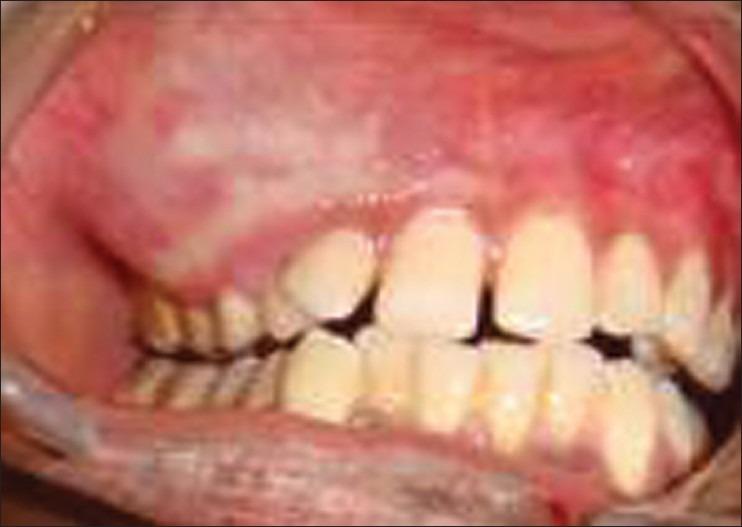

Hemangiomatous ameloblastoma (HA), which is a rare ameloblastic variant, is presented in a 15-year-old boy in the maxillary right molar region associated with unerupted canine and premolars. Radiologic and computed tomographic analysis was suggestive of cystic lesion. An histology picture confirmed the diagnosis of HA. There are less than eight cases documented in the literature and mostly are in the middle age with mandibular location. This is first ever reported case of HA in a 15-year-old boy with maxillary location. Due to less number of documented cases and no long-term follow-ups, clinical behavior and prognosis of this lesion are uncertain. In this case report, the clinical, histological, and radiographic features of HA are presented.

血管瘤样成釉细胞瘤(HA)是一种罕见的成釉细胞变异型,发生于一名15岁男孩的右上颌磨牙区,与未萌出的尖牙和前磨牙相关。放射学和计算机断层扫描分析提示为囊性病变。组织学图像确诊为HA。文献记载的病例少于8例,大多数发生于中年,位于下颌骨。这是首次报道的发生于15岁上颌骨的HA病例。由于记录在案的病例数量较少且缺乏长期随访,该病变的临床行为和预后尚不确定。本病例报告展示了HA的临床、组织学和影像学特征。